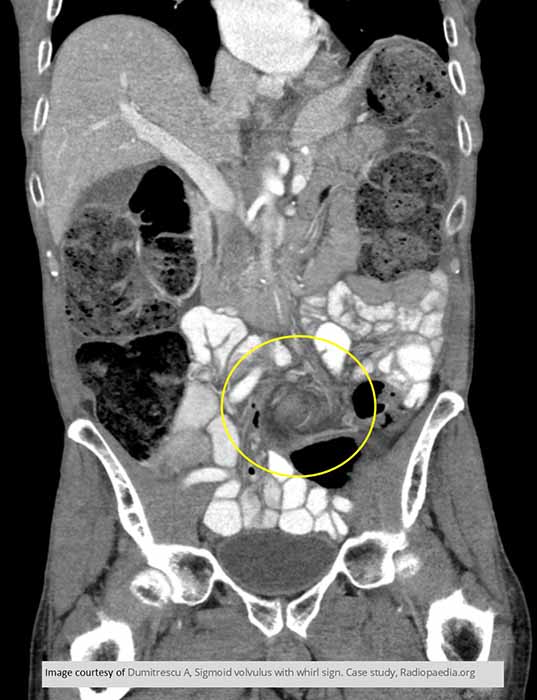

Where does volvulus most commonly occur?

In the cecum and sigmoid colon. (image shows cecal volvulvus)

Which age group commonly experiences sigmoid volvulus?

How does sigmoid volvulus occur?

The sigmoid twists on its mesenteric axis, rotating left or right.

What are the two major dangers of volvulus?

Bowel obstruction and compromised blood supply.

What can compromised blood supply lead to in volvulus?

Necrosis and gangrene.